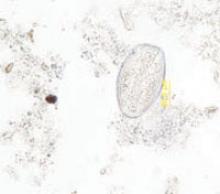

FIGURE 2

Ova

Aspiration on colonoscopy revealed football-shaped eggs that were flat on one side.